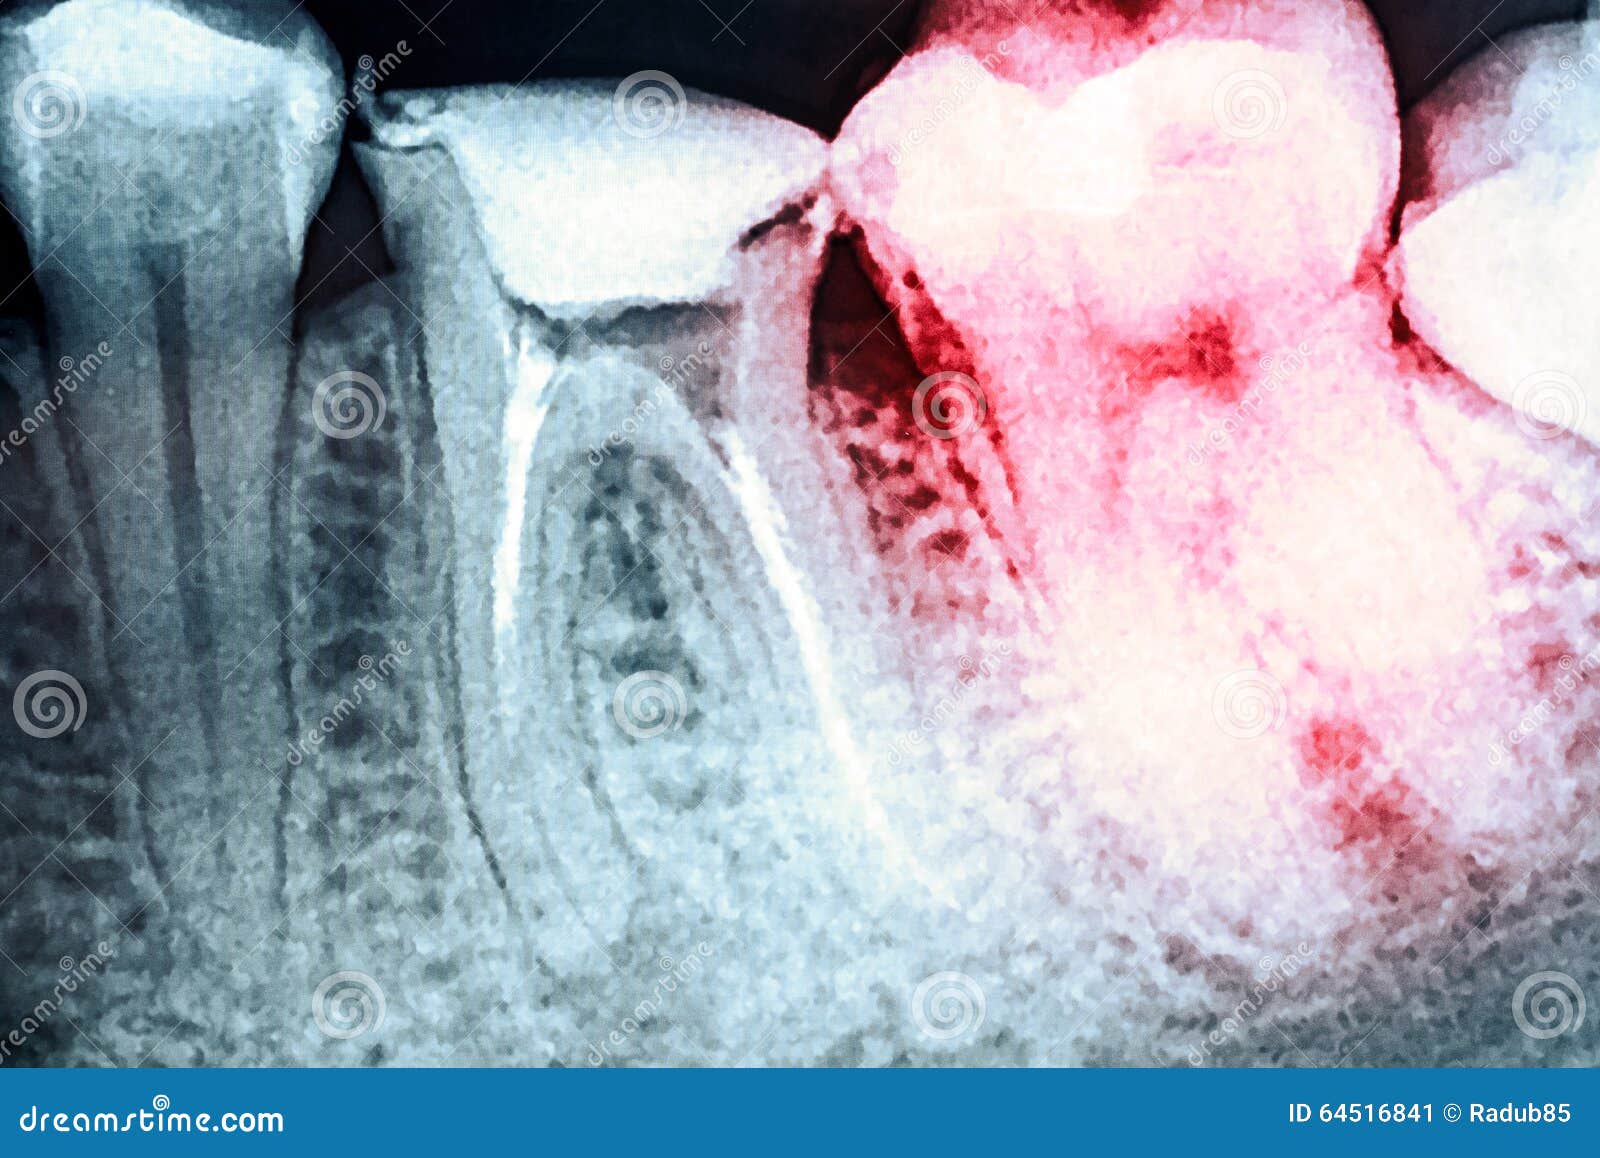

Pain of Tooth Decay on Teeth XRay Stock Image Image of beam Tooth Pain After X Ray The most common cause of tooth pain is infection. Where the pain could be coming from. Due to their close proximity, your body may be confused and perceive it as a toothache while it is actually something else. The important thing is to talk to Most dental pain is caused by an organic problem such as dental caries, periodontitis, pulpitis,. Tooth Pain After X Ray.

From www.dreamstime.com